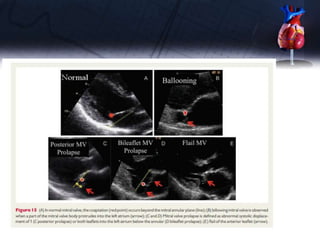

• The TTE parasternal short-axis view and the TOE transgastric view at

08 permit the assessment of the six scallops and, with colour Doppler

imaging, the localization of the origin of the regurgitant jet may identify

prolapsing segments. The TTE parasternal long-axis and the TOE

sagittal view at 1208 classically show A2 and P2.

• In apical four-chamber view, appreciation of A3, A2, and P1 (internal to

external) is possible as the TTE two-chamber view or the TOE view at

408 to 608 with TOE displays P3, A2, and P1 (left to right, bi-

commissural view). The precise location of the involved leaflets/

scallops, the description of the presence and extent of calcifications

and the extent of anatomic changes are fundamental parameters to be

provided. A flail leaflet, a ruptured papillary muscle or a large

coaptation defect is specific for severe MR.